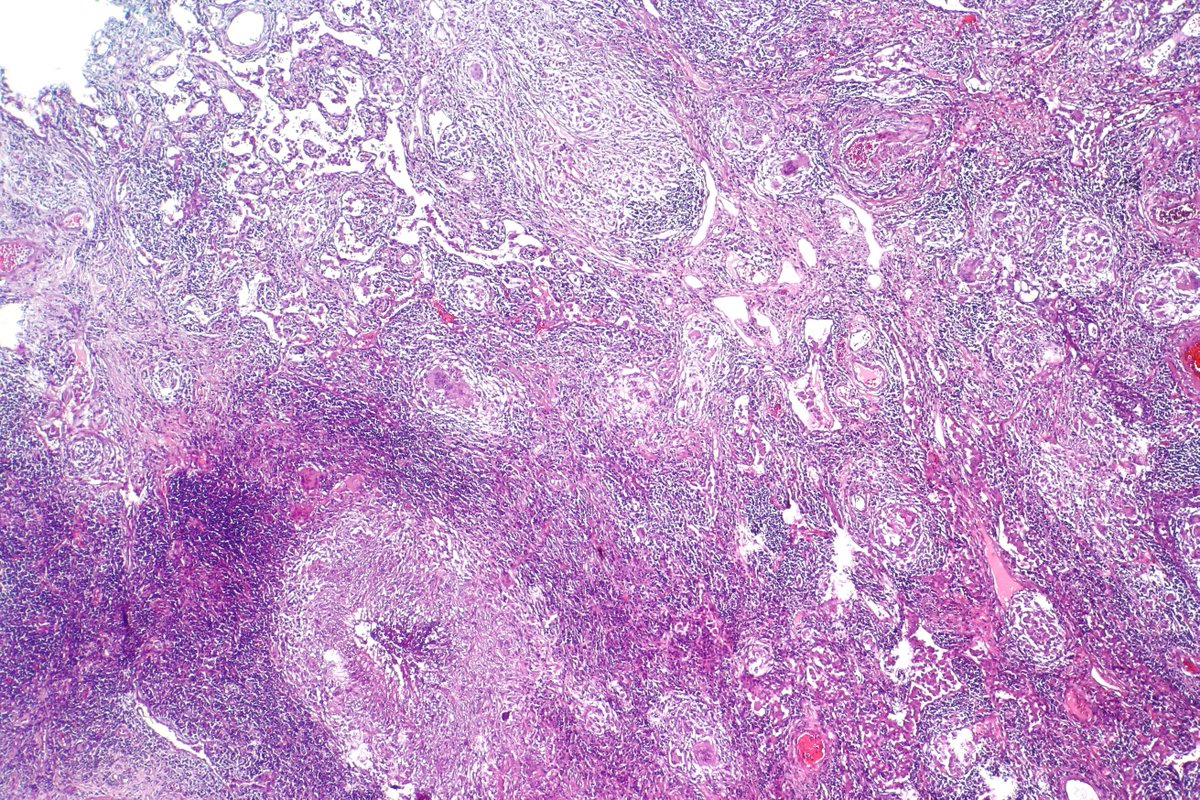

Type B2 Thymoma showing prominent large epithelial cells admixed with numerous lymphocytes. #pathology #PulmPath